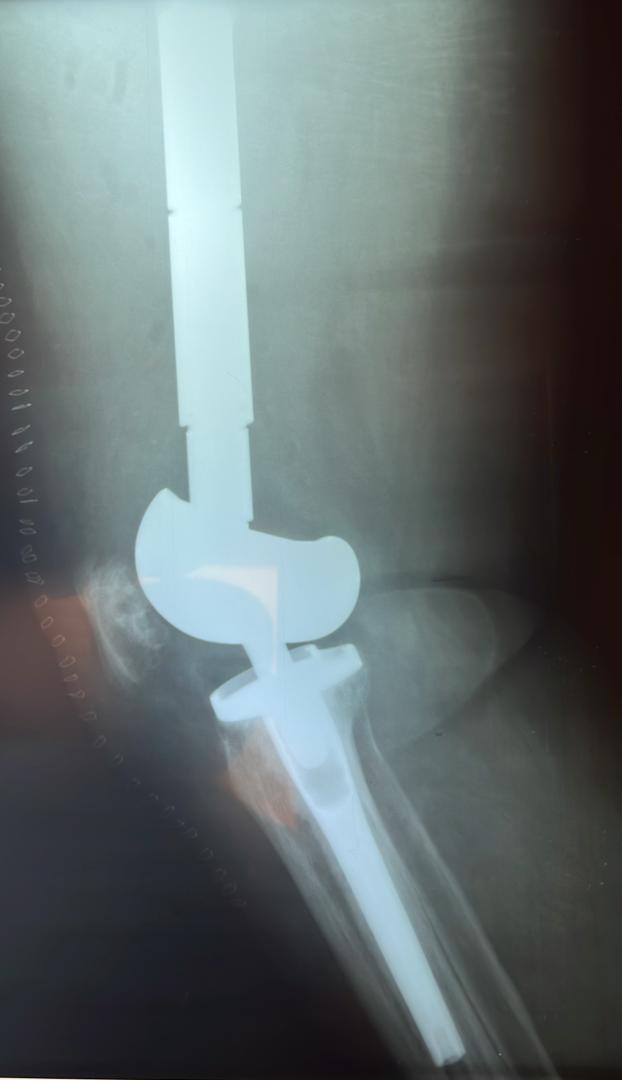

Galerie d’implants & imagerie

Exemples pédagogiques de prothèses et d’ostéosynthèses pratiquées à la CCL.

PTG — profil